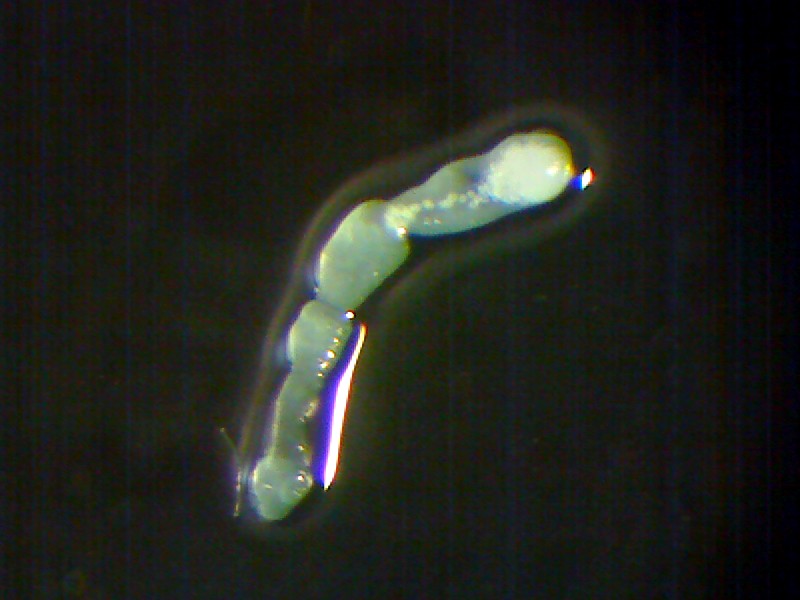

Ako vyzerá táto améba pod mikroskopom?

V laboratóriách Medirex tieto parazity diagnostikujeme priamym mikroskopickým dôkazom, kultivačným dôkazom aj farbiacimi technikami. Vieme rozlíšiť jednotlivé štádiá (trofozoit, dvojbičíkaté štádium, cysta), ktoré majú špecifickú morfológiu a štruktúru.

Mikroskopickým dôkazom možno pozorovať v odobratom likvore [mozgovomiechový mok, pozn. red.] infikovaného pacienta trofozoity [pohyblivé štádiá parazita spôsobujúce ochorenie, pozn. red.].

Podrobnejšiu štruktúru trofozoitov možno identifikovať aj po farbení podľa Giemsa. Pre parazita je po kultivácii typické rýchle rozmnožovanie. V tekutom prostredí sa dajú pozorovať dvojbičíkaté štádiá.